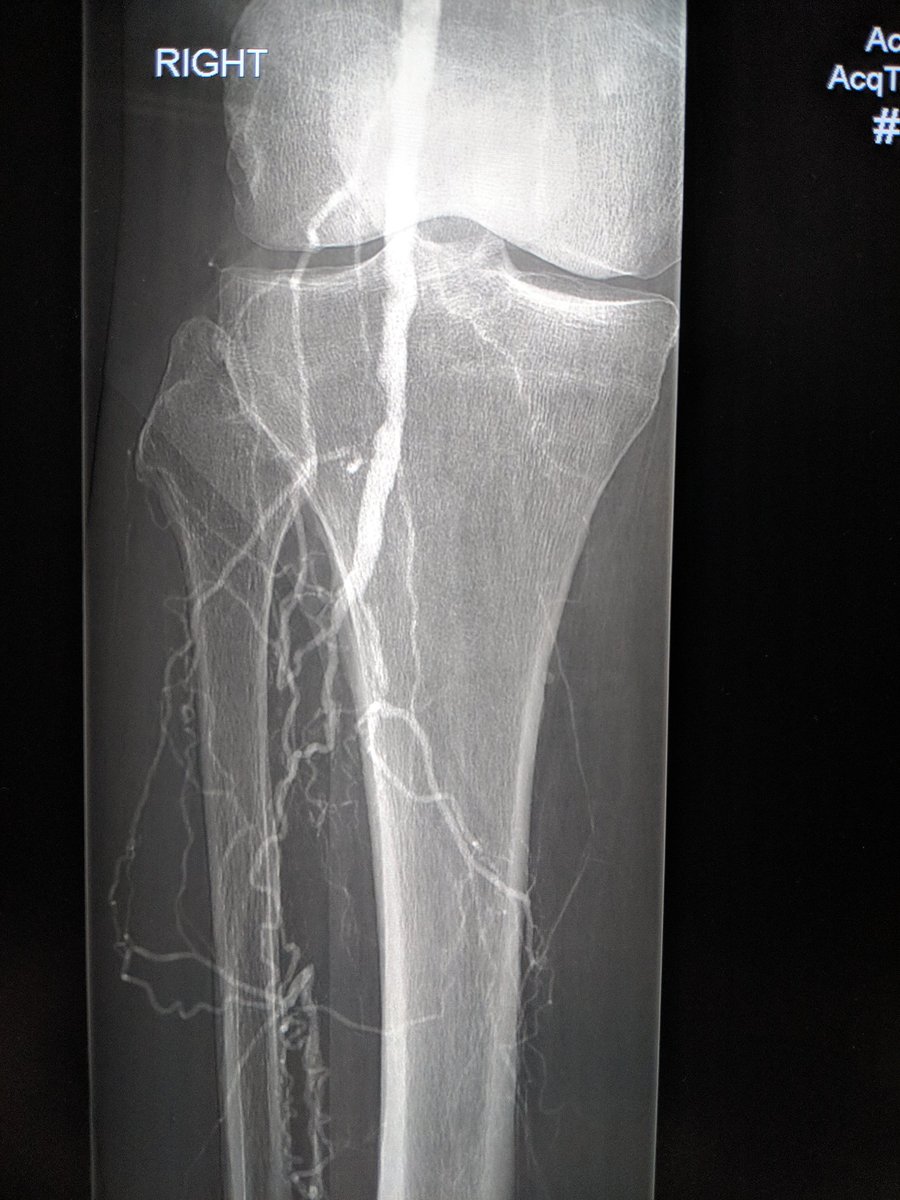

82 yo F with R5 ulcers of 3rd & 4th toes. #IRad can help with infrapopliteal and pedal revascularization to #StopTheChop. #mylegmylife #CLIFighters @SIRspecialists @SIRRFS @CLI_Global @AMPSymposium @pj_rochon

AlexCVIR's tweet image. 82 yo F with R5 ulcers of 3rd & 4th toes. #IRad can help with infrapopliteal and pedal revascularization to #StopTheChop. #mylegmylife #CLIFighters @SIRspecialists @SIRRFS @CLI_Global @AMPSymposium @pj_rochon